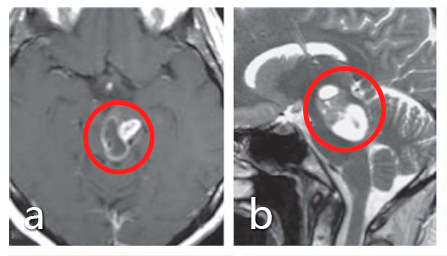

30岁女士,有复视和轻微右侧偏瘫。

术前:术前轴位(a)及矢状位(b)MRI显示,中脑内以被盖部为主的病灶呈部分实性、部分囊性,并呈明显对比增强;其下部的囊性成分向上延及脑桥上部。患者最初接受立体定向囊肿抽吸和间质放疗,并被诊断为毛细胞型星形细胞瘤,但肿瘤仍在生长。